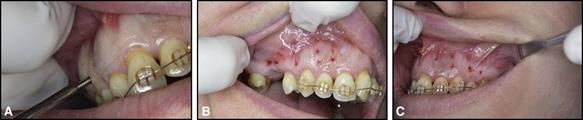

Fig. 3. Microperforaciones realizadas con la inserción y recuperación repetidas de A, mini tornillos en los lados B, derecho y C, izquierdo del maxilar. Este enfoque requiere el uso de más de 1 mini tornillo porque la cabeza pierde su borde después de varias penetraciones.

Los estudios iniciales en animales y humanos demostraron el potencial del método para promover un movimiento más rápido, pero quedan varias preguntas con respecto a la frecuencia de las microperforaciones (con qué frecuencia deberían repetirse) y el número de microperforaciones (cuántas veces deberían repetirse). y si la tasa es variable en diferentes pacientes). A nivel práctico, se encuentran disponibles kits comerciales de microperforación que permiten al ortodoncista "marcar" la profundidad de la microperforación (p. Ej., 2-3 mm). Este método también se puede aplicar a través de la inserción y extracción repetidas de mini tornillos de ortodoncia (Fig. 3).